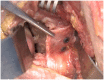

Results: The incidence of anterior shoulder instability events in the military occurs at an order of magnitude greater than in civilian populations, with rates as high as 3% per year among high-risk groups. With more than 90% risk of a Bankart lesion and high risk for instability recurrence, the military has advocated for early intervention of first-time shoulder instability while documenting up to 76% relative risk reduction versus nonoperative treatment. Preoperative evaluation with advanced radiographic imaging should be used to evaluate for attritional bone loss or "off-track" engaging defects to guide comprehensive surgical management. With complex recurrent shoulder instability and/or cases of clinically significant osseous lesions, potential options such as remplissage, anterior open capsular procedures, or bone augmentation procedures may be preferentially considered.